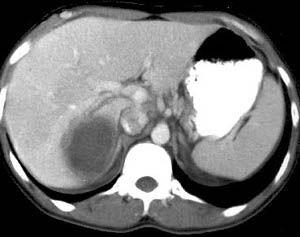

阿米巴肝脓肿是由于溶组织阿米巴滋养体从肠道病变处经血流进入肝脏,使肝发生坏死而形成,实为阿米巴结肠炎的并发症,但也可无阿米巴结肠炎而单独存在。以长期发热、右上腹或右下胸痛、全身消耗及肝脏肿大压痛、血白细胞增多等为主要临床表现,且易导致胸部并发症。回盲部和升结肠为阿米巴结肠炎的好发部位,该处原虫可随肠系膜上静脉回到肝右叶,故肝右叶脓肿者占绝大部分。那么就有患者提出阿米巴肝脓肿的症状,今天来和大家分享这个问题。

相关图片